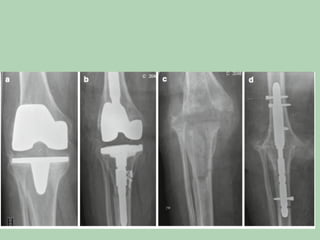

Post-Opera*ve	Infec*on	in	Closed

Fractures	Treated	with	Internal

Fixa*on

•  The	aim:

– avoid	a	chronic	infec*on.

– avoid	infected	pseudarthrosis.

•  Early	and	late.

– 4	weeks.

•  Within	4	weeks:

– radical	so^-*ssue	debridement,	harves*ng	of

*ssue	biopsies	for	culture	and	wound	closure.

– Stable??.

•  A^er	4	weeks:

– The	implant	should	be	removed.

– Ext	fixa*on.